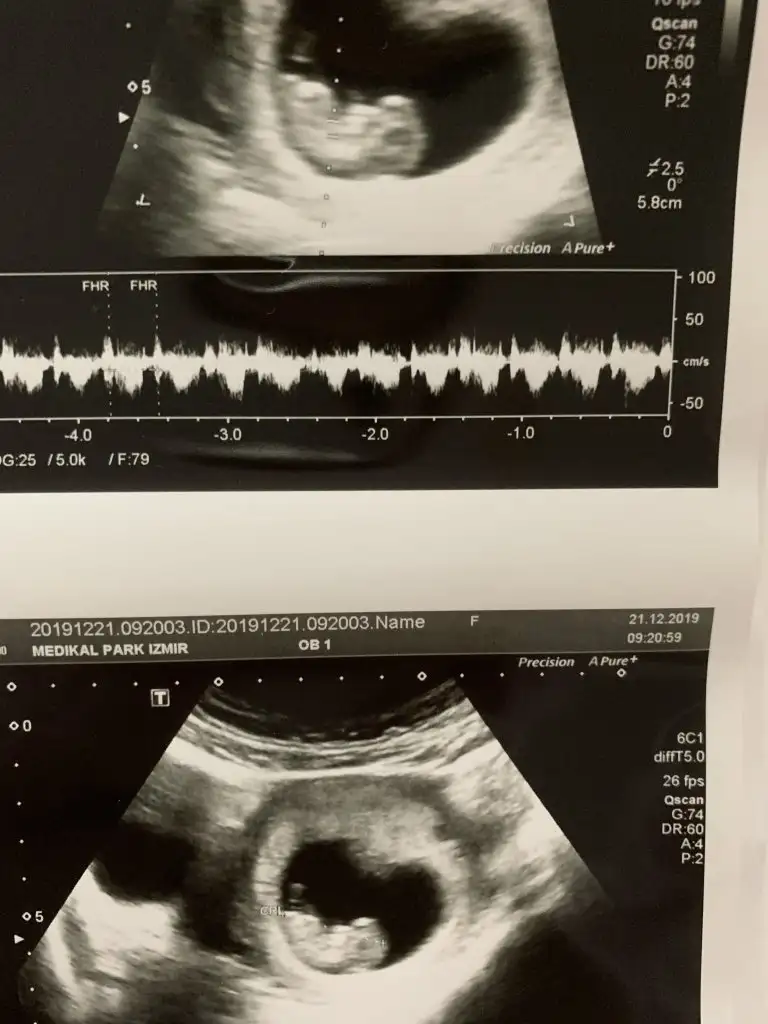

Ikra meyra 8 haftalik oldu kaldi 4 hafta bakalim kismet ne olucak.😊